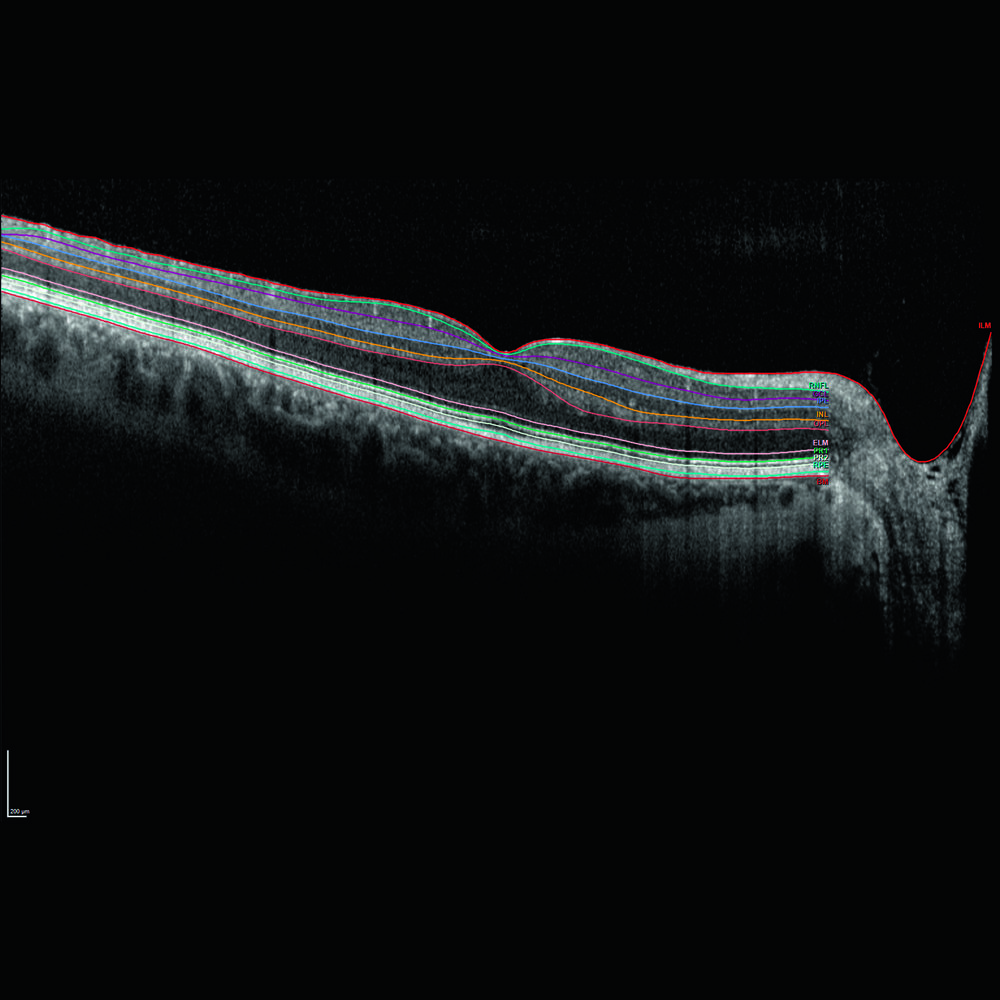

Glaucoma Module Premium Edition per Heidelberg Spectralis OCT è l’evoluzione diagnostica nel campo del glaucoma. Si tratta di un modulo opzionale applicabile su tutti i sistemi OCT basato su un concetto innovativo che rende tutte le misurazioni e la loro correlazione con database normativo oggettive e assolutamente più precise. Il modulo GMPE è dotato del sistema APS (Anatomic Positionig System), evoluzione del brevettato LiveEyeTracking (TrueTrack) di Heidelberg consente al sistema di individuare automaticamente la fovea ed il centro del nervo ottico così da allineare ogni esame alla specifica anatomia del paziente eliminando perciò tutti gli artefatti derivanti dalla correlazione con database in caso di tilting. Con la semplice esecuzione di due esami combinati il software permette di analizzare i fasci della neurorima (MRW-BMO MinimumRimWith-BruchMembrainOpening), le fibre peripapillari a tre distanze (RNFL con circle scan dedicata a tre diametri: 3,5mm-4,1mm-4,7mm) e tutto il polo posteriore sia in struttura che in asimmetria di spessore a tutti i livelli di stratificazione retinica (segmentazione a 10 strati retinici per topografia di spessore e valutazione anche del singolo strato GCL). Glacoma Module Premium Edition è anche il più valido aiuto per seguire il paziente nel tempo, sempre basato sul DNA Spectralis garantisce un riesame con mergine di errore di 1micron e genera automaticamente un grafico di progressione per ogni modalità di rielaborazione disponibile ad ulteriore completamento di un pacchetto diagnostico Premium che aggiunge un ulteriore tassello al imaging multimodale di Spectralis.